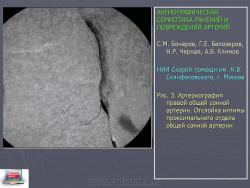

Выраженный артериовенозный сброс и объемная перегрузка правых полостей сердца могут стать причиной появления симптомов сердечной недостаточности [6]. Артериовенозные соустья обнаружены у 7,2% обследованных пациентов. Отслойка интимы ангиографически выявляется по наличию дополнительной структуры в просвете сосуда (рис. 3).

Рис. 3. Артериография правой общей сонной артерии. Отслойка интимы проксимального отдела общей сонной артерии

В результате закрытой травмы может произойти разрыв интимы, без каких-либо повреждений внешних слоев сосудистой стенки. Результатом этого может быть отслойка интимы. Нередко подобная травма сосудов является результатом повреждений опорно-двигательного аппарата, таких как переломы или вывихи суставов, при этом сосуды подвергаются растяжению в результате дислокации.

При закрытых повреждениях вследствие особенностей механизма травмы (ушиб, сдавление, размозжение или перерастяжение) наблюдаются следующие изменения сосудов: контузия стенки с ее разрывом, образование внутрисосудистой гематомы, отслойка интимы. Субинтимальная гематома может продолжить отслоение интимы. Продолжающееся отслоение интимы приводит к тому, что ее фрагменты флотируют в просвете сосуда, усугубляя отслоение и увеличивая препятствие кровотоку с каждым пульсовым толчком. Процесс заканчивается тромбозом (окклюзия) сегмента артерии (рис. 4). Это было одним из самых частых проявлений травматического повреждения артерий и встретилось в 28,8% наблюдений.